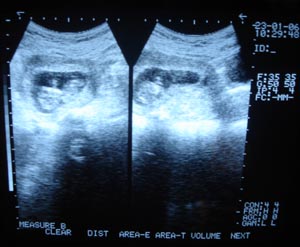

Obstetric Ultrasonography 1st trimester

The routine includes that confirm the number of gestation. Locate its position (r/o ectopic). Measure CRL crown rump length & match with the h/o LMP (last menstrual period)